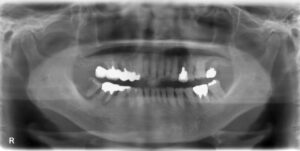

上下8本欠損症例

BEFORE AFTER 77歳女性/上下7本/インプラント埋込手術 【治療内容】 以前は義歯を使用されていましたが、お…